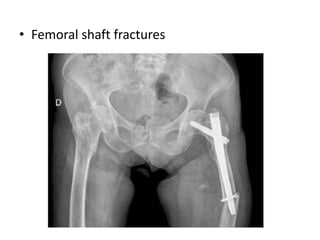

• Femoral shaft fractures

Thigh pain –in uncemented cases Femoral fractures

• Screw cutout – mainly following incorrect placement of screws